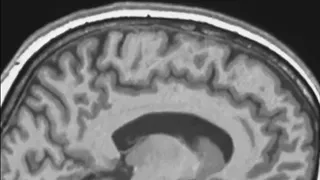

Научными исследователями обнаружено, что наш мозг может продолжать вою работу и после смерти человека. Согласно результатам эксперимента, проведенного канадскими учеными, сотрудниками университета Западного Онтарио, ученые и сделали такой вывод. В рамках эксперимента ученые исследовали активность мозга умерших пациентов. Так вот, мозг одного из них работал еще около десяти минут с того момента, как зафиксирована остановка сердца.

Кроме того, специалистами были замечены мозговые волны, встречающиеся у человека, когда тот находится в глубоком сне. По мнению ученых, это нонсенс для науки.

Как выяснилось, мозг после смерти способен продолжать работу лишь у одного из четырех пациентов. Кроме того, врачами отмечено, что активность мозга в первые секунды после смерти продолжается благодаря неким физическим, а не духовным процессам. Несмотря на это, в истории медицины известны случаи, когда люди просыпались после того, как у них была зафиксирована остановка сердца. После этого, у них кардинально менялось мировоззрение, чаще всего они начинали искренне верить и служить Богу. Ученые же, которым доводилось слышать рассказы выживших про «свет в конце тоннеля», склонны считать это просто галлюцинацией, вызванной воздействием остановки сердца на мозг пациента.